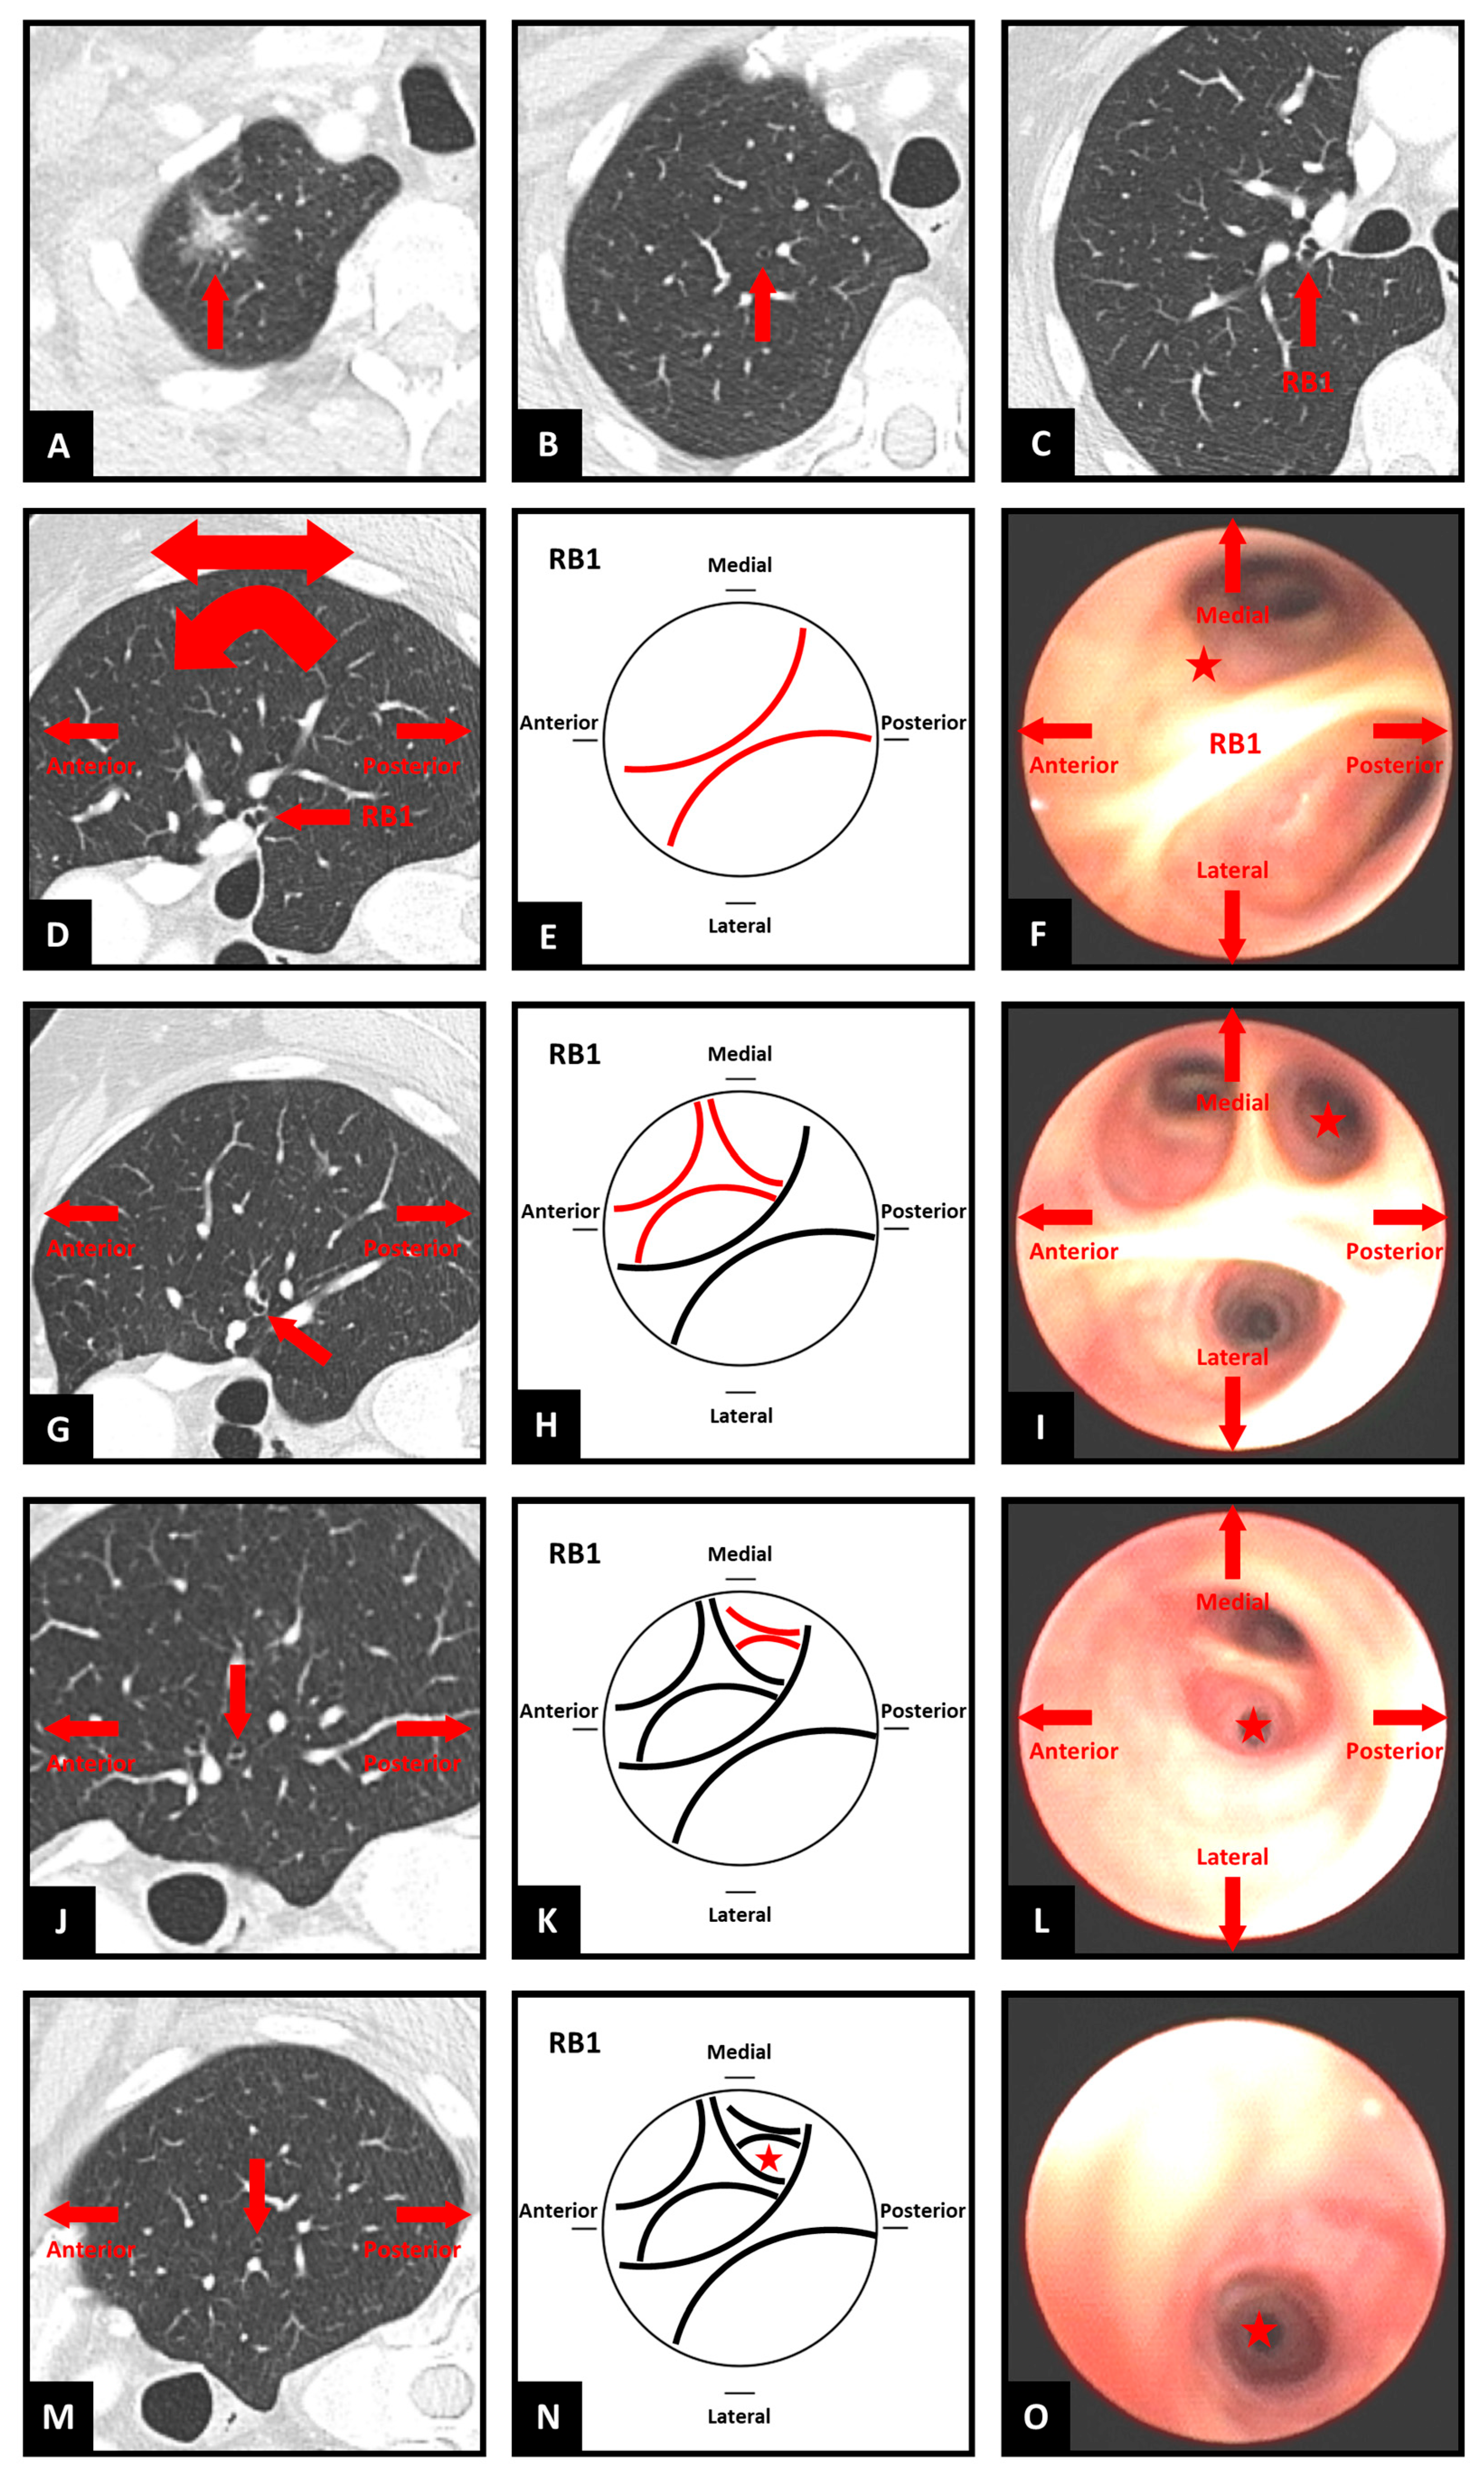

Step 1. Choose the destination and identify the segmental airway (Figure 1A–C)

To identify which segmental airway leads to the target, first identify the sub-segmental airway that leads to the target (if a bronchus sign is present) or is most favorable for accessing the target (if no bronchus sign is present). Then, move through the CT slices to progress proximally through the preceding generations of airways to arrive at the ostium of the segmental airway.

Step 2. Transform the CT image—optional (Figure 1D)

Transformation (flipping and/or rotation) of the CT image is not essential, provided the bronchoscopist can maintain a spatial awareness of the anatomical directions as they draw the map. These anatomical directions are often marked on the edges of the CT images as well. Each bronchoscopist can therefore decide if they prefer to perform such transformations on the CT image or in their mind. However, it may be more instinctive if axial images are transformed in a manner that assists the bronchoscopist in imagining themselves navigating the CT images as if they were performing the bronchoscopy. Therefore, the authors suggest initially flipping the image horizontally to reflect the anatomical orientation as the bronchoscope enters the trachea, then rotating 90 degrees clockwise or counterclockwise for left and right-sided lesions, respectively. This reflects the rotation of the bronchoscope as occurs when the left or right main bronchus is intubated. Subsequent transformations may be natural for some users, such as flipping the CT image vertically for upper lobe lesions in the apical segments. It may also be helpful to use sagittal reconstructions for laterally projecting segmental airways and coronal reconstructions for anteriorly/posteriorly projecting segmental airways. Because the ostium of a segmental airway is rarely facing in a precise anatomical direction, consider either using the closest direction or a combination of axial and reconstructed CT images side-by-side. Potential combinations are suggested in

Figure 2, although considering the individual anatomy on a case-by-case basis is most reliable.

Step 3. Determine the starting position and orientation (Figure 1F)

Imagine yourself positioned as the bronchoscope at the ostium of the segmental airway that leads to the target. Using the CT images, establish your orientation relative to the patient as you directly face to enter the segmental airway. What part of the patient is above and below you, and to your left and right? Match these four directions with their closest corresponding anatomical directions (superior, inferior, medial, lateral, anterior, posterior). Existing familiarity with flexible bronchoscopy is essential to understanding how the bronchoscope will be positioned. As segmental airways rarely align with precise anatomical directions, consider either using the closest direction or a combination, for example, antero-lateral, postero-medial, etc.

Step 4. Draw the segmental ostium (Figure 1E)

Draw a circle, which represents the bronchoscopic view at the ostium of the segmental airway, then indicate the four anatomical directions around the circle. This forms the basis for the map.

Step 5. Find the next generation (Figure 1G)

Starting at the segmental ostium, move through the CT slices and imagine you are proceeding along the airway until you identify the next carina/generation. There will be either two or three branches. By moving back and forth, determine the relative position and anatomical direction of these two or three branches. For example, one branch may be projecting more medially in relation to another branch projecting more laterally

Inside the circle, draw an arc corresponding to each branch in the approximate position relative to the other branch(es) and direction relative to the four anatomical directions around the circle. Try to approximately reflect the relative sizes of the branches on the map. Remember that the map does not need to be perfect. So long as the relative anatomical direction of each airway is accurately reflected, the map will achieve its purpose of guiding the choice between the branches at each carina/generation.

Step 7. Map subsequent generations to the target airway (Figure 1J–L)

Repeat the process (from step 5) for each successive generation of airway leading to the target or destination airway, drawing arcs within the respective preceding arcs.

Step 8. Mark the target airway on the map (Figure 1M–O)

If there are multiple sub-segmental airways that lead to the target, you can indicate multiple options on the map.

Figure 1.

Steps of simplified bronchial branch tracing. RB1 = right upper lobe apical segment bronchus. ★ symbol indicates target airway for navigation. (A–C) Identifying the segmental airway; (D) CT image transformation; (E) Drawing the segmental ostium; (F) Starting position and orientation; (G) Finding the next generation; (H,I) Drawing the branches; (J–L) Mapping the generations; (M–O) Marking the target airway.

Figure 1.

Steps of simplified bronchial branch tracing. RB1 = right upper lobe apical segment bronchus. ★ symbol indicates target airway for navigation. (A–C) Identifying the segmental airway; (D) CT image transformation; (E) Drawing the segmental ostium; (F) Starting position and orientation; (G) Finding the next generation; (H,I) Drawing the branches; (J–L) Mapping the generations; (M–O) Marking the target airway.